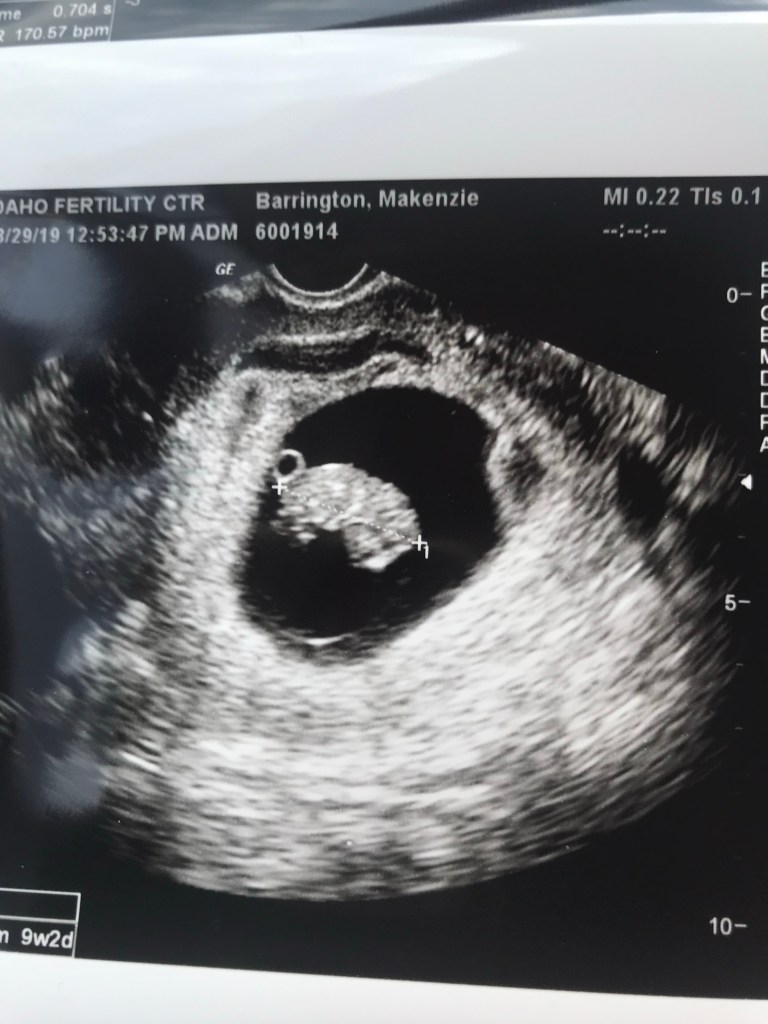

The next ultrasound was 2 weeks later and was my last one with the fertility clinic. After that I was to move to my regular OBGYN for the rest of the pregnancy.

When we got this picture my mom said it looked like a baby pig so that’s all I see now when I look at it.